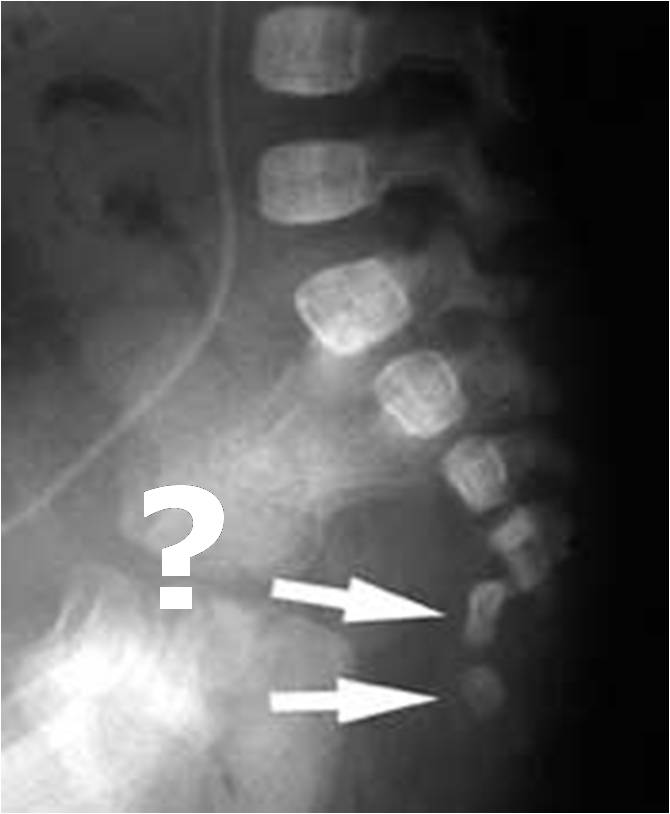

Fractura del cuerpo vertebral o subluxación

Fractura luxación del sacro. Niña 2 meses de edad. Versión original: “Se cayó de una mesa”. Más tarde el novio de la madre confesó que la lanzó bruscamente contra el piso